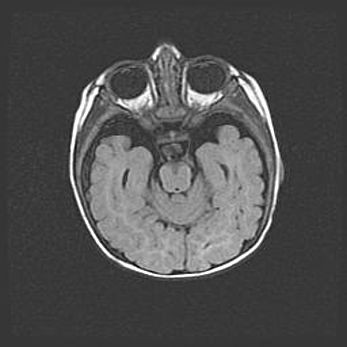

Неполная лизэнцефалия (пахигирия). Открытая гидроцефалия.

Возраст: 17 дней

Вес: 3110 г

Пол: мужской

Окружность головы: 33,5 см

Срок гестации: 35-36 недель

Лизэнцефалия—недоразвитие корковой пластинки и мозговых извилин в результате нарушения миграции нейронов коры. Поверхность мозговых полушарий гладкая. Микроскопически выявляется отсутствие нормальных слоев коры и скопление групп нейронов в подкорковом белом веществе.

Пахигирия—уменьшение числа вторичных извилин. В пораженном полушарии нервные клетки образуют толстый недифференцированный слой с неправильно расположенными нервными волокнами и группами гетеротопных клеток. Нервные клетки незрелые. Белое вещество истончено. При этом нередко аномально развит корково-спинномозговой путь.